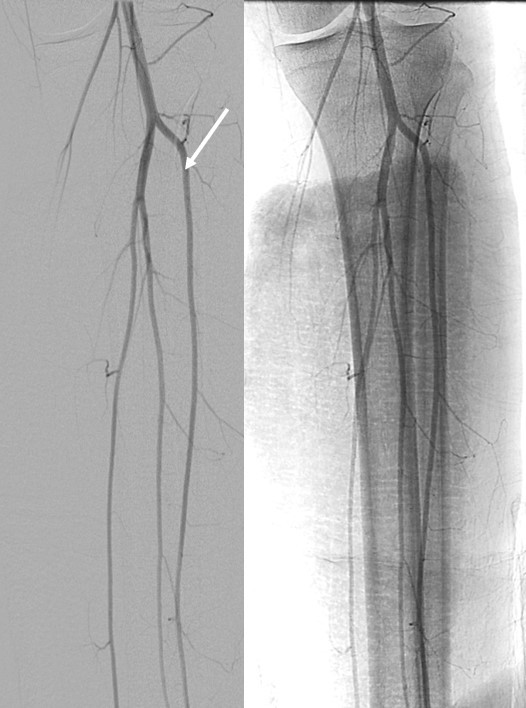

what is a potential complication of embolization of the selected vessel?

ovarian artery is selected in the right image.

Potential complication of ovarian failure

This is a pt with uterine fibroids with some blood supply coming from an enlarged ovarian artery